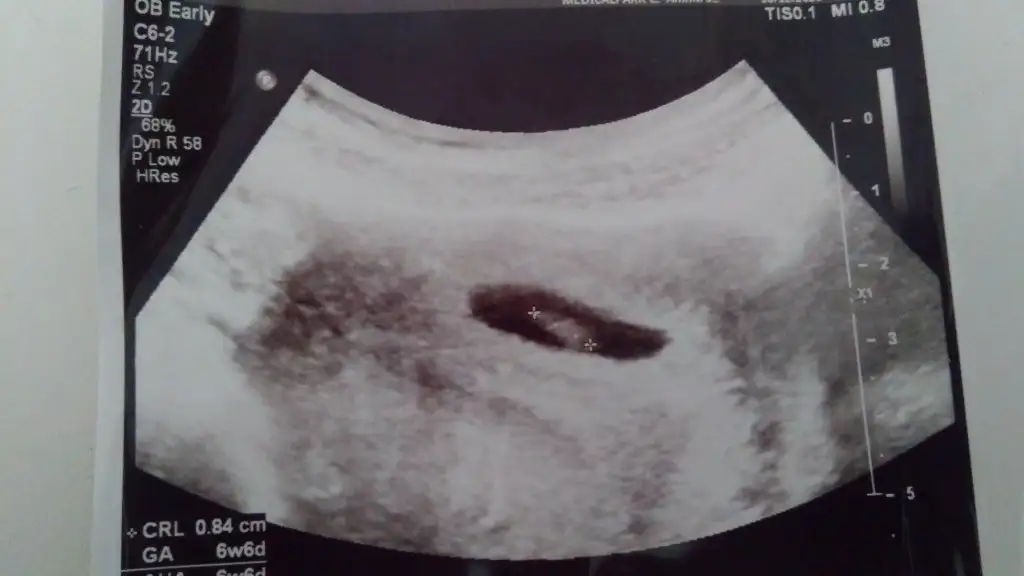

En iyi 11 12 13 haftalar olmalı şimdilik sanki erkek yinede istediğim haftalar olursa paylasin10.hafta acaba belli olan bişi var mı☺

En iyi 11 12 13 haftalar olmalı şimdilik sanki erkek yinede istediğim haftalar olursa paylasin